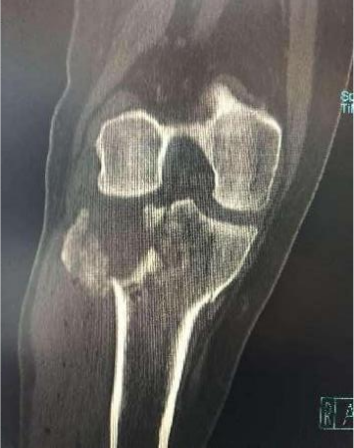

2、图3-6 术前CT见胫骨平台严重塌陷、劈裂

胫骨平台骨折的病人,如果在30年前大多数医院应该会选择保守治疗。那时CT尚未普及,而仅凭X片会低估其损伤的严重程度,容易产生可不必手术的假象,也难以准确判断骨折移位情况。即使想做手术,也没有什么好的内固定可供选用。

保守治疗肯定会遗留

膝关节功能障碍

、创伤性关节炎、跛行及畸形,造成残疾,而现在,我们采用积极的手术治疗让患者恢复了正常的外观及功能。